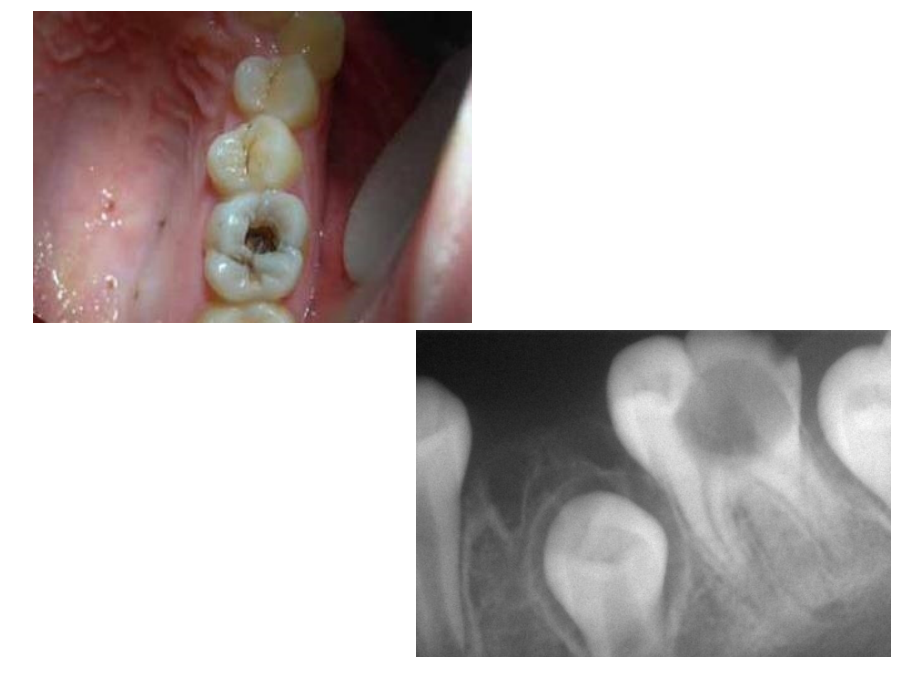

单击此处编辑母版标题样式,单击此处编辑母版文本样式,第二级,第三级,第四级,第五级,*,*,*,儿童龋病的治疗和预防,龋病是儿童青少年常见病,多发病,世界卫生组织(WHO)已将龋病列为仅次于癌症和心血管病的第三种非传染性疾病。,乳牙龋齿患病特点,1、发病早,患龋率高,2、龋齿多发,范围广,3、龋蚀发展速度快,急性龋多见,4、自觉症状不明显,易忽略,5、修复性牙本质形成活跃,利于早期防治,乳牙,龋病治疗的目的:,1、,终止,龋蚀的发展,,保护,牙髓的正常活动,,避免,因龋而引起的并发症;,2、,恢复,牙体的外形和咀嚼功能,维持牙列的完整性,使乳牙能正常地被替换,有利于颌骨的生长发育,乳牙龋病的治疗,1.药物治疗,:,适应症:广泛浅龋或剥脱状的环状龋,不易制备洞形,距离替换器较近。,步骤:修正外形;清除牙面、干燥防湿;,涂药:操作时应反复涂擦2-3分钟,每周涂1-2次。,药物:氟化物(氟化钠、氟化亚锡、氟化甘油等),2.修复治疗,:,最好在早期阶段,去除腐质,制备洞形,用牙科材料行充填术,恢复其牙体外形.,这时治疗既简单,也无痛苦。,年轻恒牙龋病的治疗方法,再矿化法,修复治疗,:减速切削、避免意外露髓、注意保护牙髓、预防性树脂充填、不强调邻面接触点的恢复。,预防性树脂充填,:去除龋坏组织;清洁牙面,冲洗、干燥、隔湿;如牙本质暴露,用氢氧化钙垫底;复合树脂充填后,涂布封闭剂;检查。,龋病的预防,控制菌斑、窝沟封闭、使用氟化物、建立健康的饮食习惯、定期进行口腔健康检查,窝沟封闭,窝沟封闭是指不去除咬合面牙体组织,在其上涂布一层粘结性树脂,保护牙釉质不受细菌及代谢产物侵蚀,增强牙齿抗龋能力,从而达到预防龋病发生的一种有效防龋方法。,为什么少年儿童要做窝沟封闭?,在儿童时期,后牙刚萌出,窝沟细而深,因此极容易存留细菌和食物残渣,而这个时候,大多数儿童喜欢吃糖、饼干等精细食物,不注意口腔卫生,因而就更容易患龋齿。医学称这一时期为龋齿“易感期”。为此,少年儿童应该尽早做窝沟封闭,窝沟封闭的适合症,1,一般来说,深窝沟,特别是可以卡住探针的(包括可疑龋);,2,患者其它牙齿,特别是对侧同名牙患龋或有患龋倾向的人应当行窝沟封闭;,3,儿童牙齿萌出后达到咬合平面即适宜作窝沟封闭,一般在萌出4年之内。,4,封闭的最佳时间是:乳磨牙34岁,第一恒磨牙67岁,第二恒磨牙1113岁,双尖牙913岁,。,窝沟封闭的步骤,